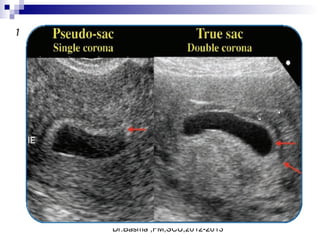

True gestational sacTrue gestational sac must bemust be differentiated fromdifferentiated from

pseudo sacpseudo sac

 Embryonic Vesicle (Primary yolk sac

 Round or oval.

 Double ring )Ring of decidualized

endometrium.

 Fundal or mid-portion of the uterus.

 May occasionally implant low down in the

uterine cavity.

Single decidul ring ( pseudo sac)

This may be due to a decidual cast and fluid in the endometrial cavity. This appearance can be found in

the presence of an ectopic pregnancy

Double ring appearance